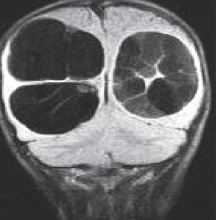

Кисты средней линии - киста прозрачной перегородки (cavum septi pellucidi), полость Верге (cavum Vergae) и киста промежуточного паруса (cavum veli interpositi) - являются нормальными структурами головного мозга плода. В течение 6 месяцев после рождения у большинства людей они запустевают, но могут и сохраниться, визуализируясь при этом на МРТ головного мозга. По-видимому, эти полости не имеют клинического значения и относятся к случайным находкам при томографии. Киста прозрачной перегородки (еще называют V желудочком) является медиальной стенкой боковых желудочков и ограничена спереди коленом мозолистого тела, сверху мозолистым телом и сзади столбами свода . Полость Верге представляет собой продолжение кисты прозрачной перегородки кзади и расположена между телами желудочков . Обычно обе кисты сочетаются. Киста промежуточного паруса расположена в крыше III желудочка (tela choroidea), между треугольниками боковых желудочков на уровне отверстий Монро. Она ограничена сверху мозолистым телом, cзади цистерной четверохолмия и снизу III желудочком.

Кисты средней линии - киста прозрачной перегородки (cavum septi pellucidi), полость Верге (cavum Vergae) и киста промежуточного паруса (cavum veli interpositi) - являются нормальными структурами головного мозга плода. В течение 6 месяцев после рождения у большинства людей они запустевают, но могут и сохраниться. По-видимому, эти полости не имеют клинического значения и относятся к случайным находкам при МРТ головного мозга . Киста прозрачной перегородки (еще называют V желудочком) является медиальной стенкой боковых желудочков и ограничена спереди коленом мозолистого тела, сверху мозолистым телом и сзади столбами свода. Полость Верге представляет собой продолжение кисты прозрачной перегородки кзади и расположена между телами желудочков (рис.105). Обычно обе кисты сочетаются. Киста промежуточного паруса расположена в крыше III желудочка (tela choroidea), между треугольниками боковых желудочков на уровне отверстий Монро. Она ограничена сверху мозолистым телом, cзади цистерной четверохолмия и снизу III желудочком.